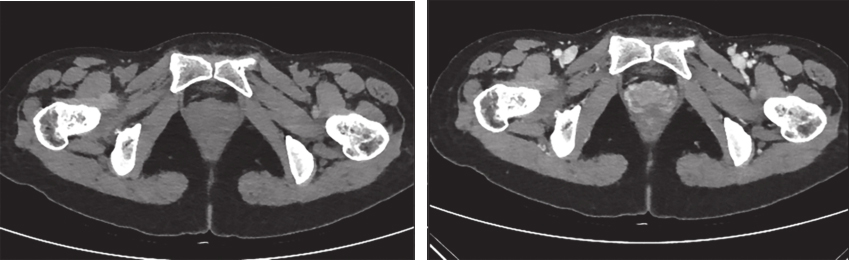

完善经直肠超声:直肠下段及肛管前壁距肛门1cm处可见不均匀低回声,大小约为4.3cm×3.7cm,内部回声不均,内部血流丰富、紊乱,可引出动脉频谱;肿瘤位于腹膜反折以下;耻骨直肠肌、肛门外括约肌完整。经腹超声见盆腔不均匀低回声,大小约5.9cm×4.8cm,与阴道分界不清。经会阴超声见盆腔不均匀低回声,大小约5.2cm×5.5cm,前方距皮肤约0.2cm,边界欠清,形态不规则,内血流信号丰富,可引出动脉频谱。完善PET-CT示:阴道下段与直肠前壁见类圆形肿物,大小约5.0cm×3.5cm×5.9cm,密度稍欠均匀,肿物与阴道、直肠前壁均分界不清,局部突向外阴。术前评估为潜在可切除性直肠GIST,考虑到肿物较大且与周围组织器官关系密切,直接切除有联合脏器切除的可能,且难以保全阴道和肛门功能,遂决定行术前靶向药物治疗。患者从2016年4月15日起,开始口服甲磺酸伊马替尼,400mg/d。此后规律复查,伊马替尼治疗1个月后复查增强CT(图2):直肠下段与阴道间可见类圆形混杂密度影,范围大致约4.2cm×2.5cm×2.6cm,病灶密度不均,其内可见液性密度区,增强扫描实性成分明显强化,病灶局部与直肠前壁及阴道后壁分界不清。对比首诊盆腔MRI,病灶较前缩小(Choi标准:PR状态)。伊马替尼治疗4个月后复查增强CT(图3):直肠下段与阴道间可见类圆形低密度病灶,大小约3.5cm×2.3cm×1.8cm,增强扫描可见轻度强化,病灶局部与直肠前壁及阴道后壁分界不清。对比前次复查:病灶较前略缩小(Choi标准:PR状态)。伊马替尼治疗6个月后复查增强CT(图4):直肠下段与阴道间可见类圆形低密度病灶,大小约3.9cm×2.1cm×1.9cm,增强扫描可见轻度强化,病灶局部与直肠前壁及阴道后壁分界不清。对比前片,病灶较前无明显改变(Choi标准:维持PR状态)。考虑患者术前靶向治疗已进行6月余,且药物治疗效果已达最大化,建议患者接受手术治疗。2016年11月1日门诊以“胃肠间质瘤,靶向治疗后”收入北京大学人民医院胃肠外科。

图4 伊马替尼术前治疗6个月后增强CT表现

引自:胃肠间质瘤典型病例诊治与解析.第1版.ISBN:978-7-117-30146-6.主编:陶凯雄 曹 晖